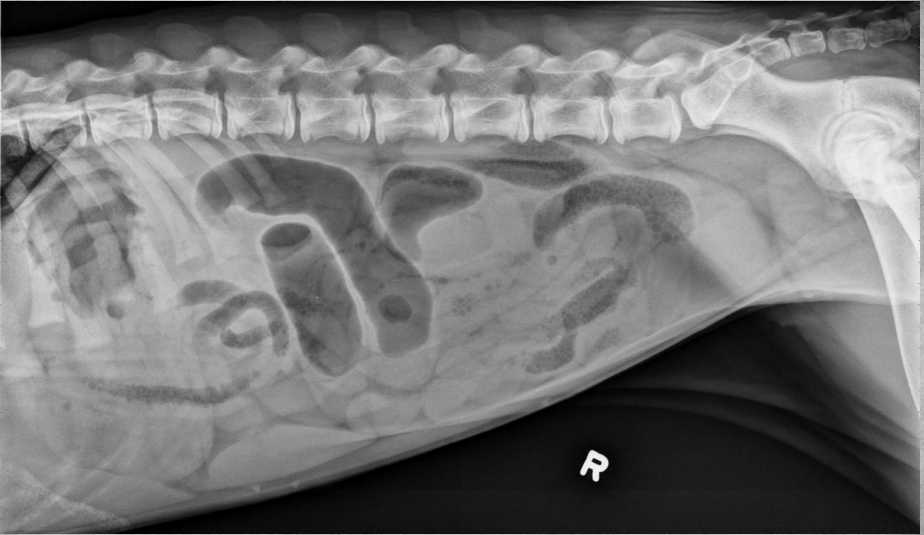

●6 mo female Great Dane

●Vomiting, loss of appetite for 3 days

●Suspected foreign body

● Entire small intestine moderately homogenously fluid filled, teeny bubbles throughout GI tract indicating GI hypomotility.

● Markedly gas-distended intestinal segment in mid-abdomen, reverse C-shaped, most likely normal caecum.

● Diffusedly fluid filled GIT with interspersed gas bubbles is most consistent with functional ileus from severe enteritis.

● No radiographically evident foreign body.

● Dx: Parvoviral enteritis